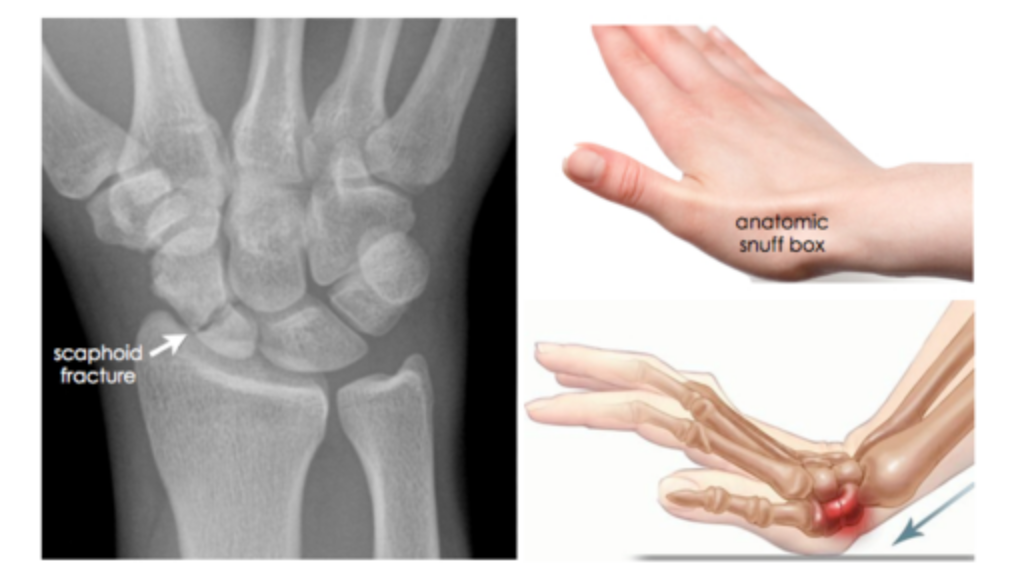

Which carpal bone is most commonly fractured? - falling on hand

scaphoid bone - which arti ulates with the radius -

compression of median nerve in carpal tunnel apace due to fracture or inflammation